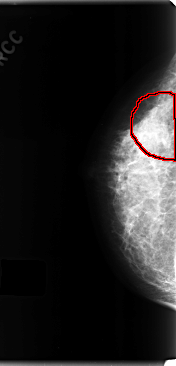

RIGHT_CC LINES 4752 PIXELS_PER_LINE 2288 BITS_PER_PIXEL 12 RESOLUTION 50 OVERLAY

FILE: C_0198_1.RIGHT_MLO.OVERLAY

TOTAL_ABNORMALITIES 1

ABNORMALITY 1

LESION_TYPE CALCIFICATION TYPE AMORPHOUS DISTRIBUTION SEGMENTAL

ASSESSMENT 4

SUBTLETY 2

PATHOLOGY MALIGNANT

TOTAL_OUTLINES 1

BOUNDARY

FILE: C_0198_1.RIGHT_CC.OVERLAY